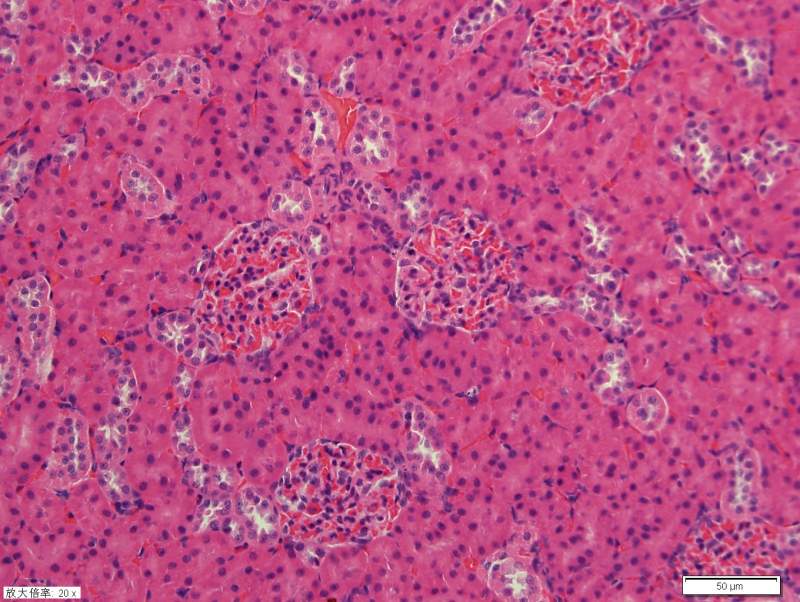

请教各位高手关于肾脏HE染色 已有1人参与